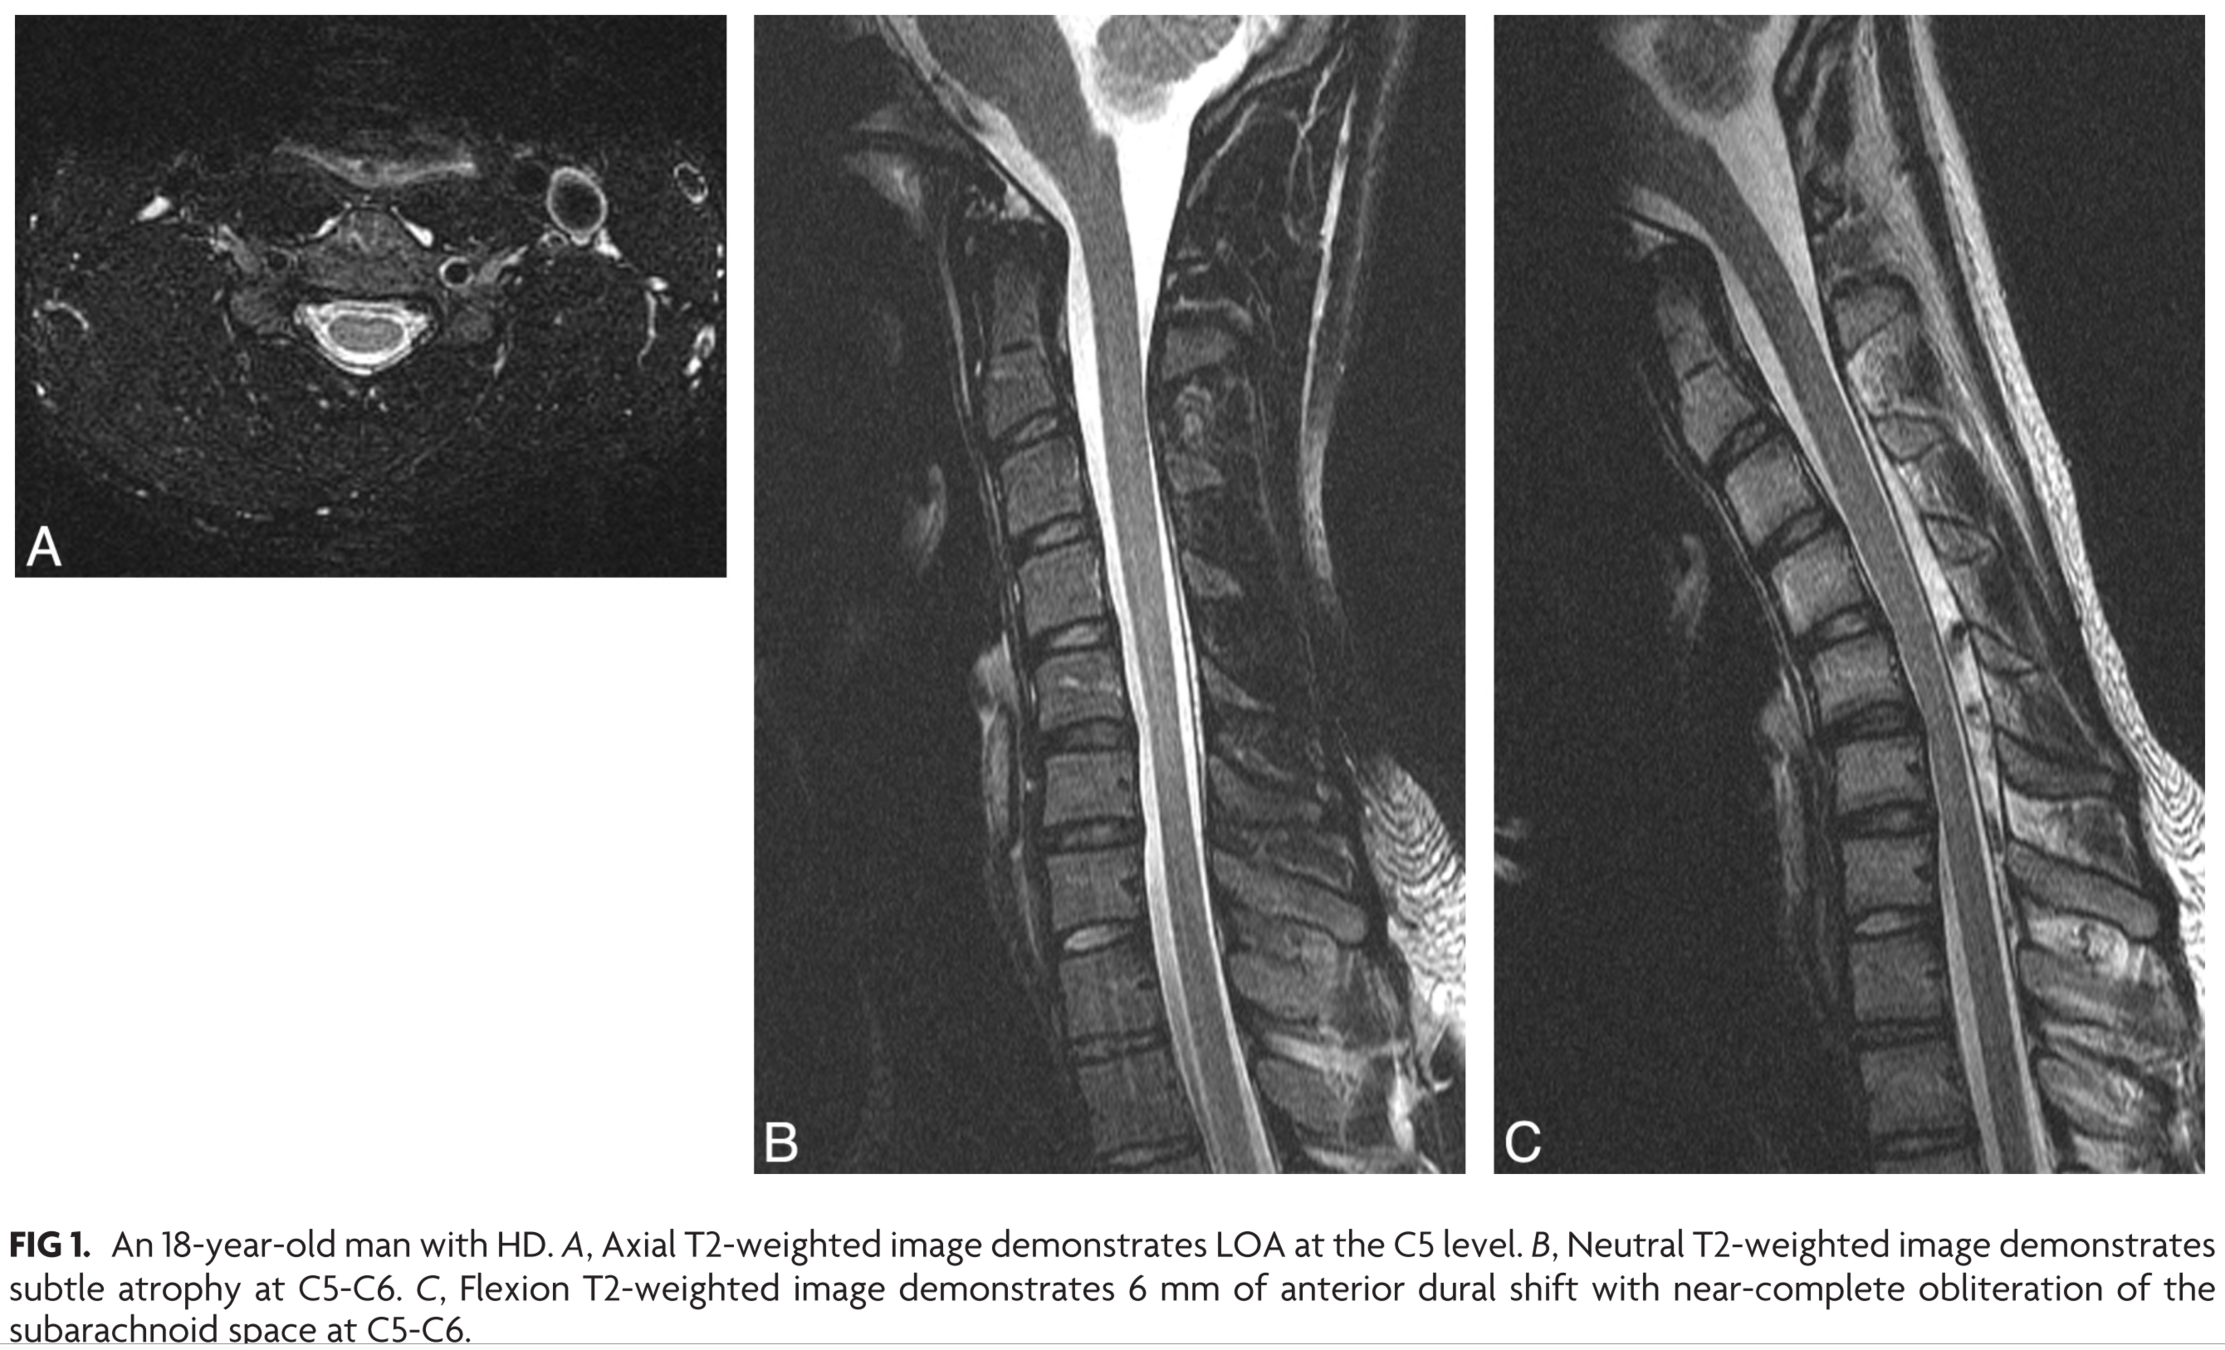

Imaging important in diagnosis

- Neutral MRI may show atrophy, T2 signal, asymmetric flattening

- Flexion MRI shows classic findings

- Posterior dural detachment -> widened LDS

- Enh of engorged posterior epidural venous plexus

- Compression of cord

- Lehman et al 2013: Sens similar for neutral and flexion (70% vs 71%), but neutral findings subtle

- Chen et al 2004: Loss of attachment 93% sensitive

- Lai et al 2011: LDS increase in 46% healthy subjects